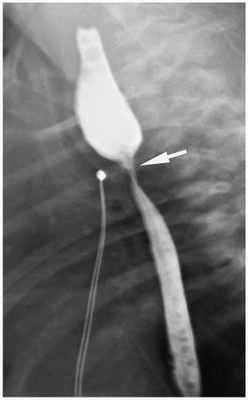

Встречаются реже, чем атрезии пищевода. Наблюдаются на любом уровне, однако чаще на уровне бифуркации трахеи. Распознаются обычно у детей старшего возраста и даже у взрослых. Различают циркулярные (в форме песочных часов или трубки) сужения пищевода, обусловленные внутриутробно возникшим фиброзом, хрящевым или мышечным кольцом, и перепончатые стенозы, вызванные своеобразной диафрагмой (мембрана) из атипично развитой слизистой оболочки, частично закрывающей просвет пищевода.

Распознаются стенозы с помощью контрастного рентгенологического исследования, во время которого выявляется равномерное, правильной формы сужение просвета пищевода, которое нередко образует фигуру двух конусов, направленных друг к другу своими вершинами. Контуры суженного участка четкие, ровные, переход его к соседним участкам плавный. Рельеф слизистой оболочки в зоне сужения не изменен, эластичность прилегающих к нему стенок не нарушена. Пищевод над сужением обычно расширен. В нем могут наблюдаться проявления сопутствующего эзофагита. При перепончатом стенозе во время рентгенологического исследования выявляют стойкую циркулярную деформацию (сужение) просвета за счет мембраны в виде тонкой симметричной ленты, полукольца или кольца, расположенных перпендикулярно длиннику пищевода.

Степень расширения вышележащих отделов пищевода зависит от величины отверстия в мембране. При подозрении на наличие мембраны пищевод необходимо исследовать с небольшим количеством контрастного вещества, чтобы не перекрыть тенью бария ее изображение. Узкие, полулунной формы неполные мембраны лучше выявляются в условиях двойного контрастирования пищевода.